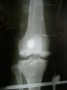

Paciente, sexo masculino, 20 anos, vítima de acidente motociclístico há 2 dias, evoluindo com dor e deformidade em joelho direito (Vide fotos).

Conduta realizada: Redução Incruenta + Fixação Transarticular (Vide fotos).